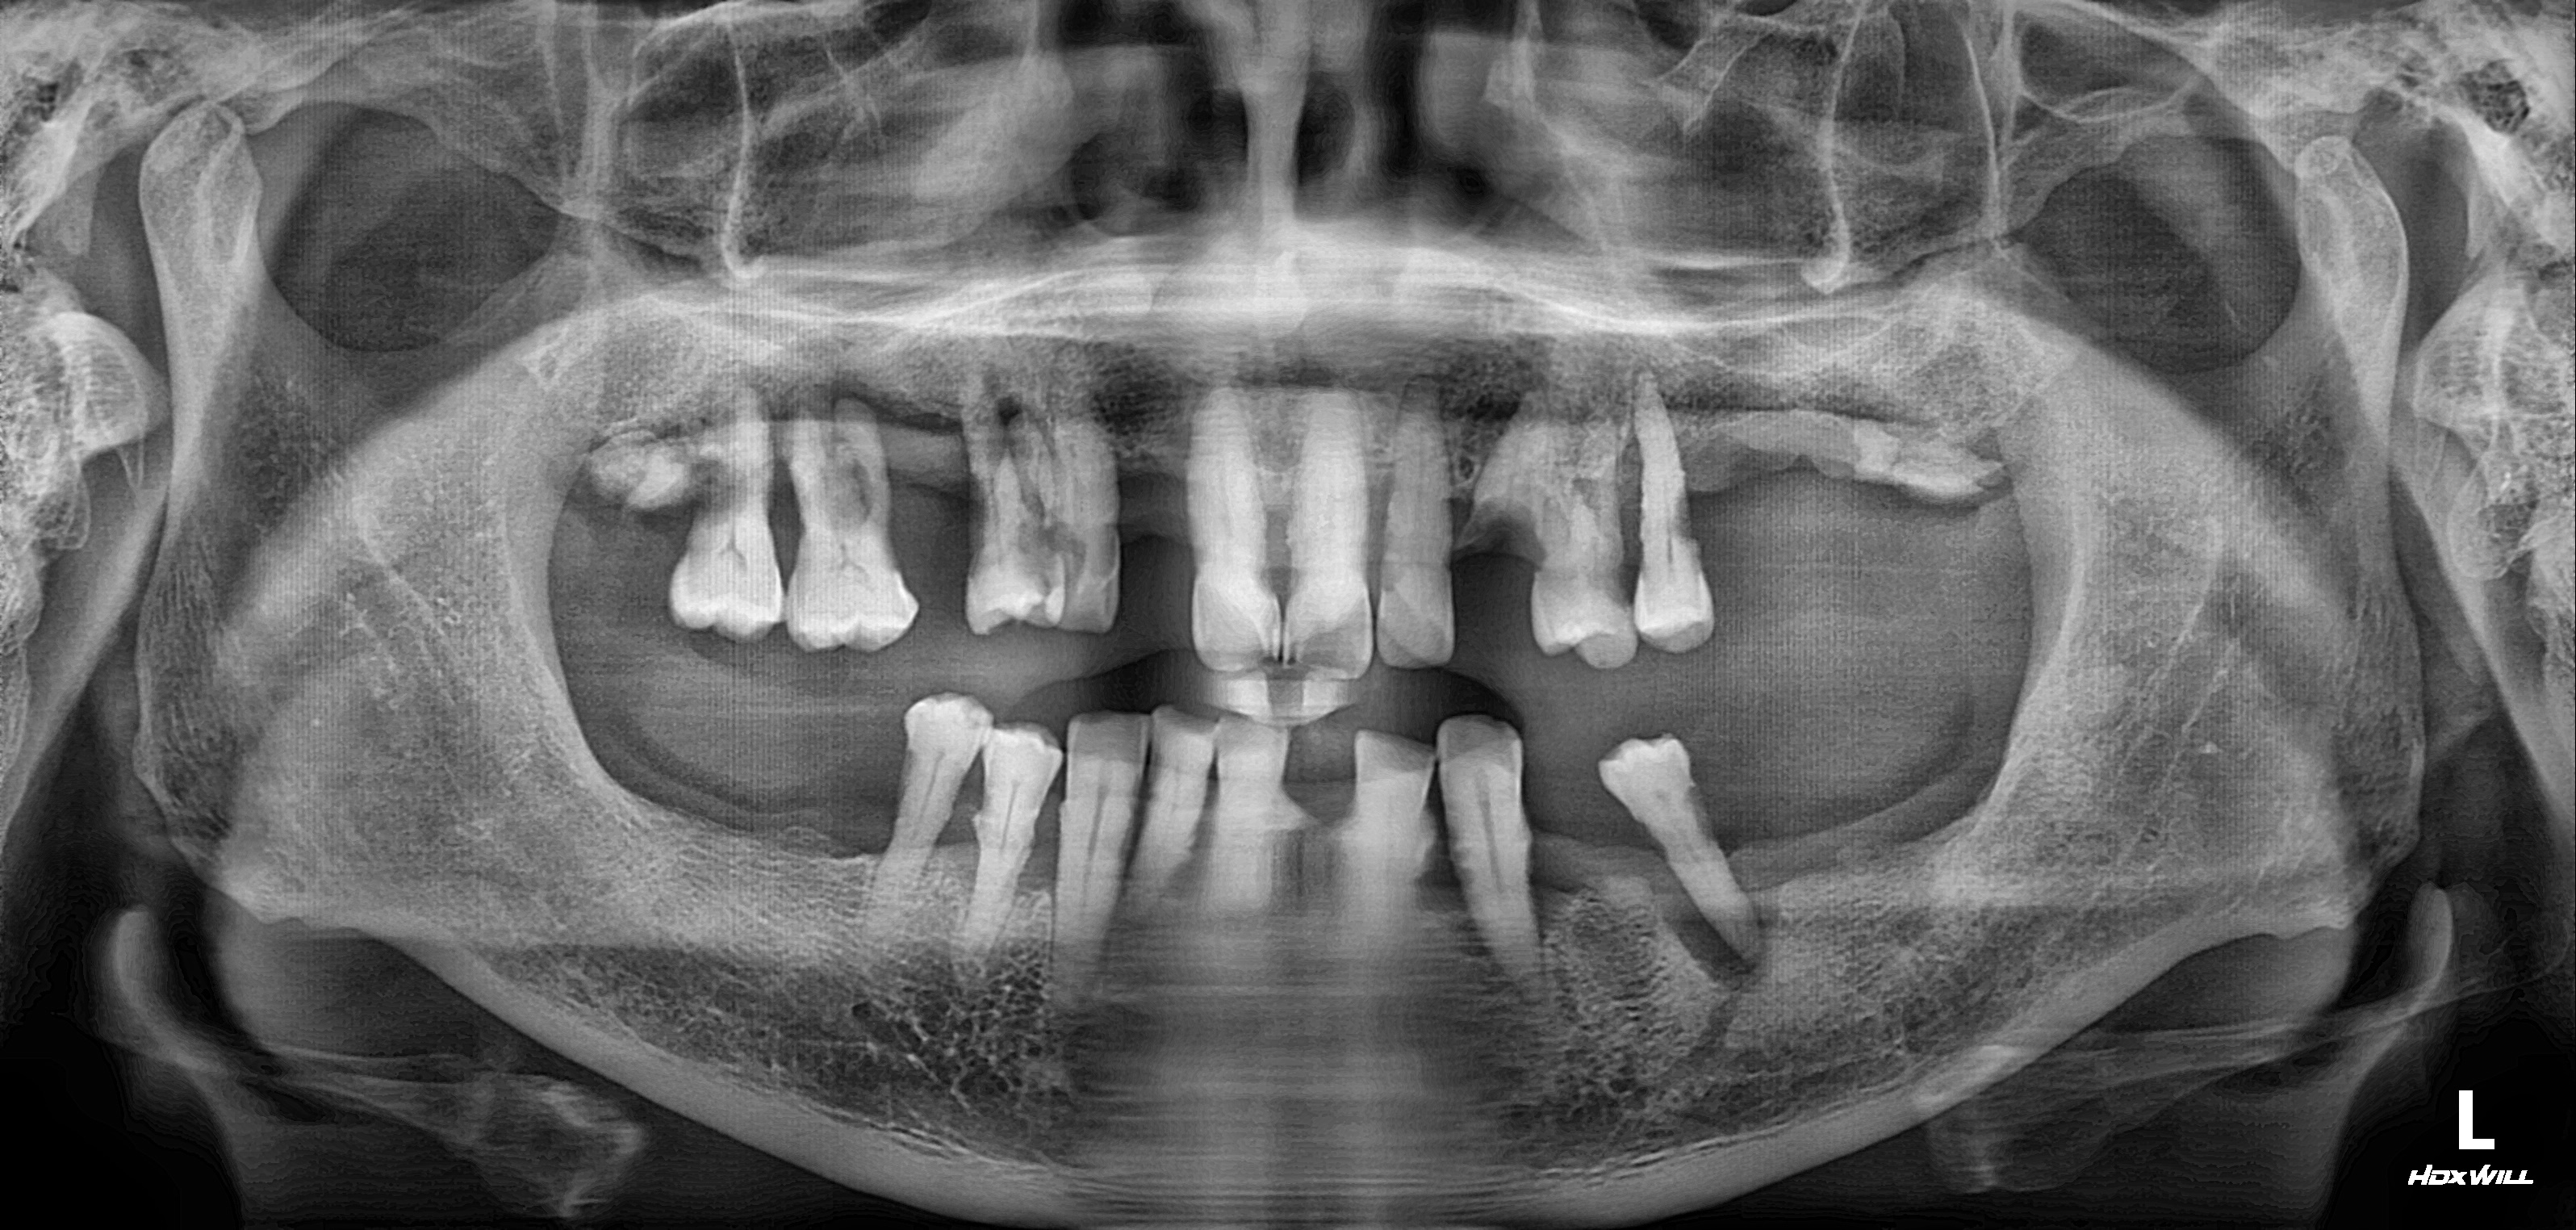

수술 전

수술 후

상악 임플란트 식립사례

전후사진